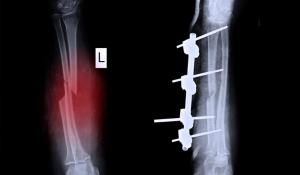

Гомілка - це частина ноги людини від коліна до стопи, яка складається з великої та малогомілкової кісток.

Перелом гомілки може трапитися внаслідок, до прикладу, падіння чи сильного удару.